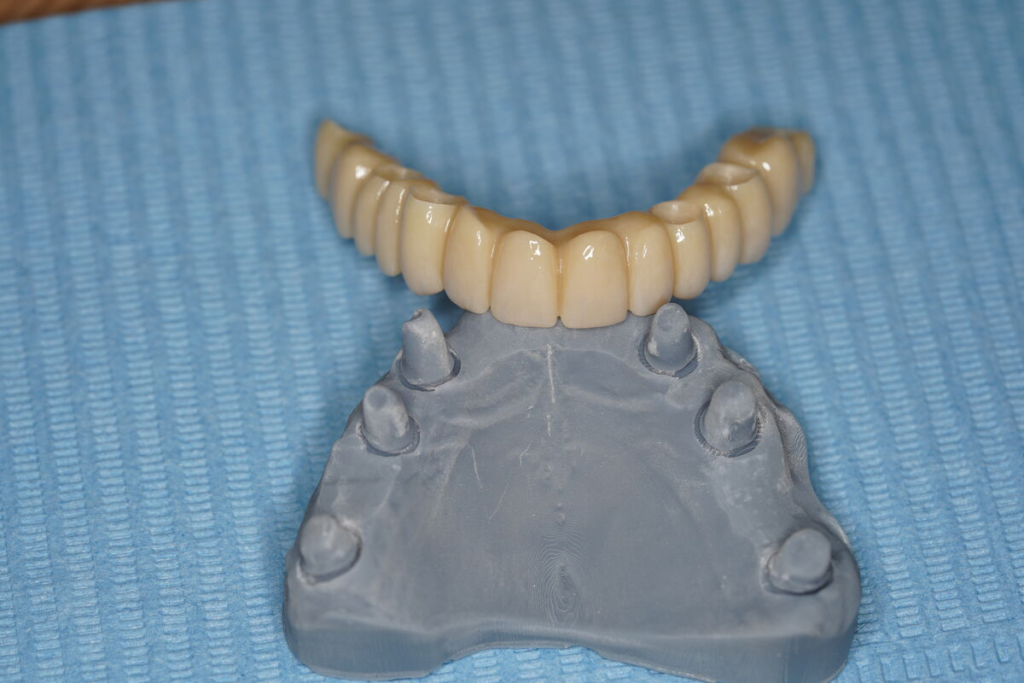

Po 4–6 měsících nasazujeme trvalý můstek.

Používáme multivrstvý zirkon pro maximální estetiku, pevnost a dlouhou životnost.

Technika All-on-X — II. fáze